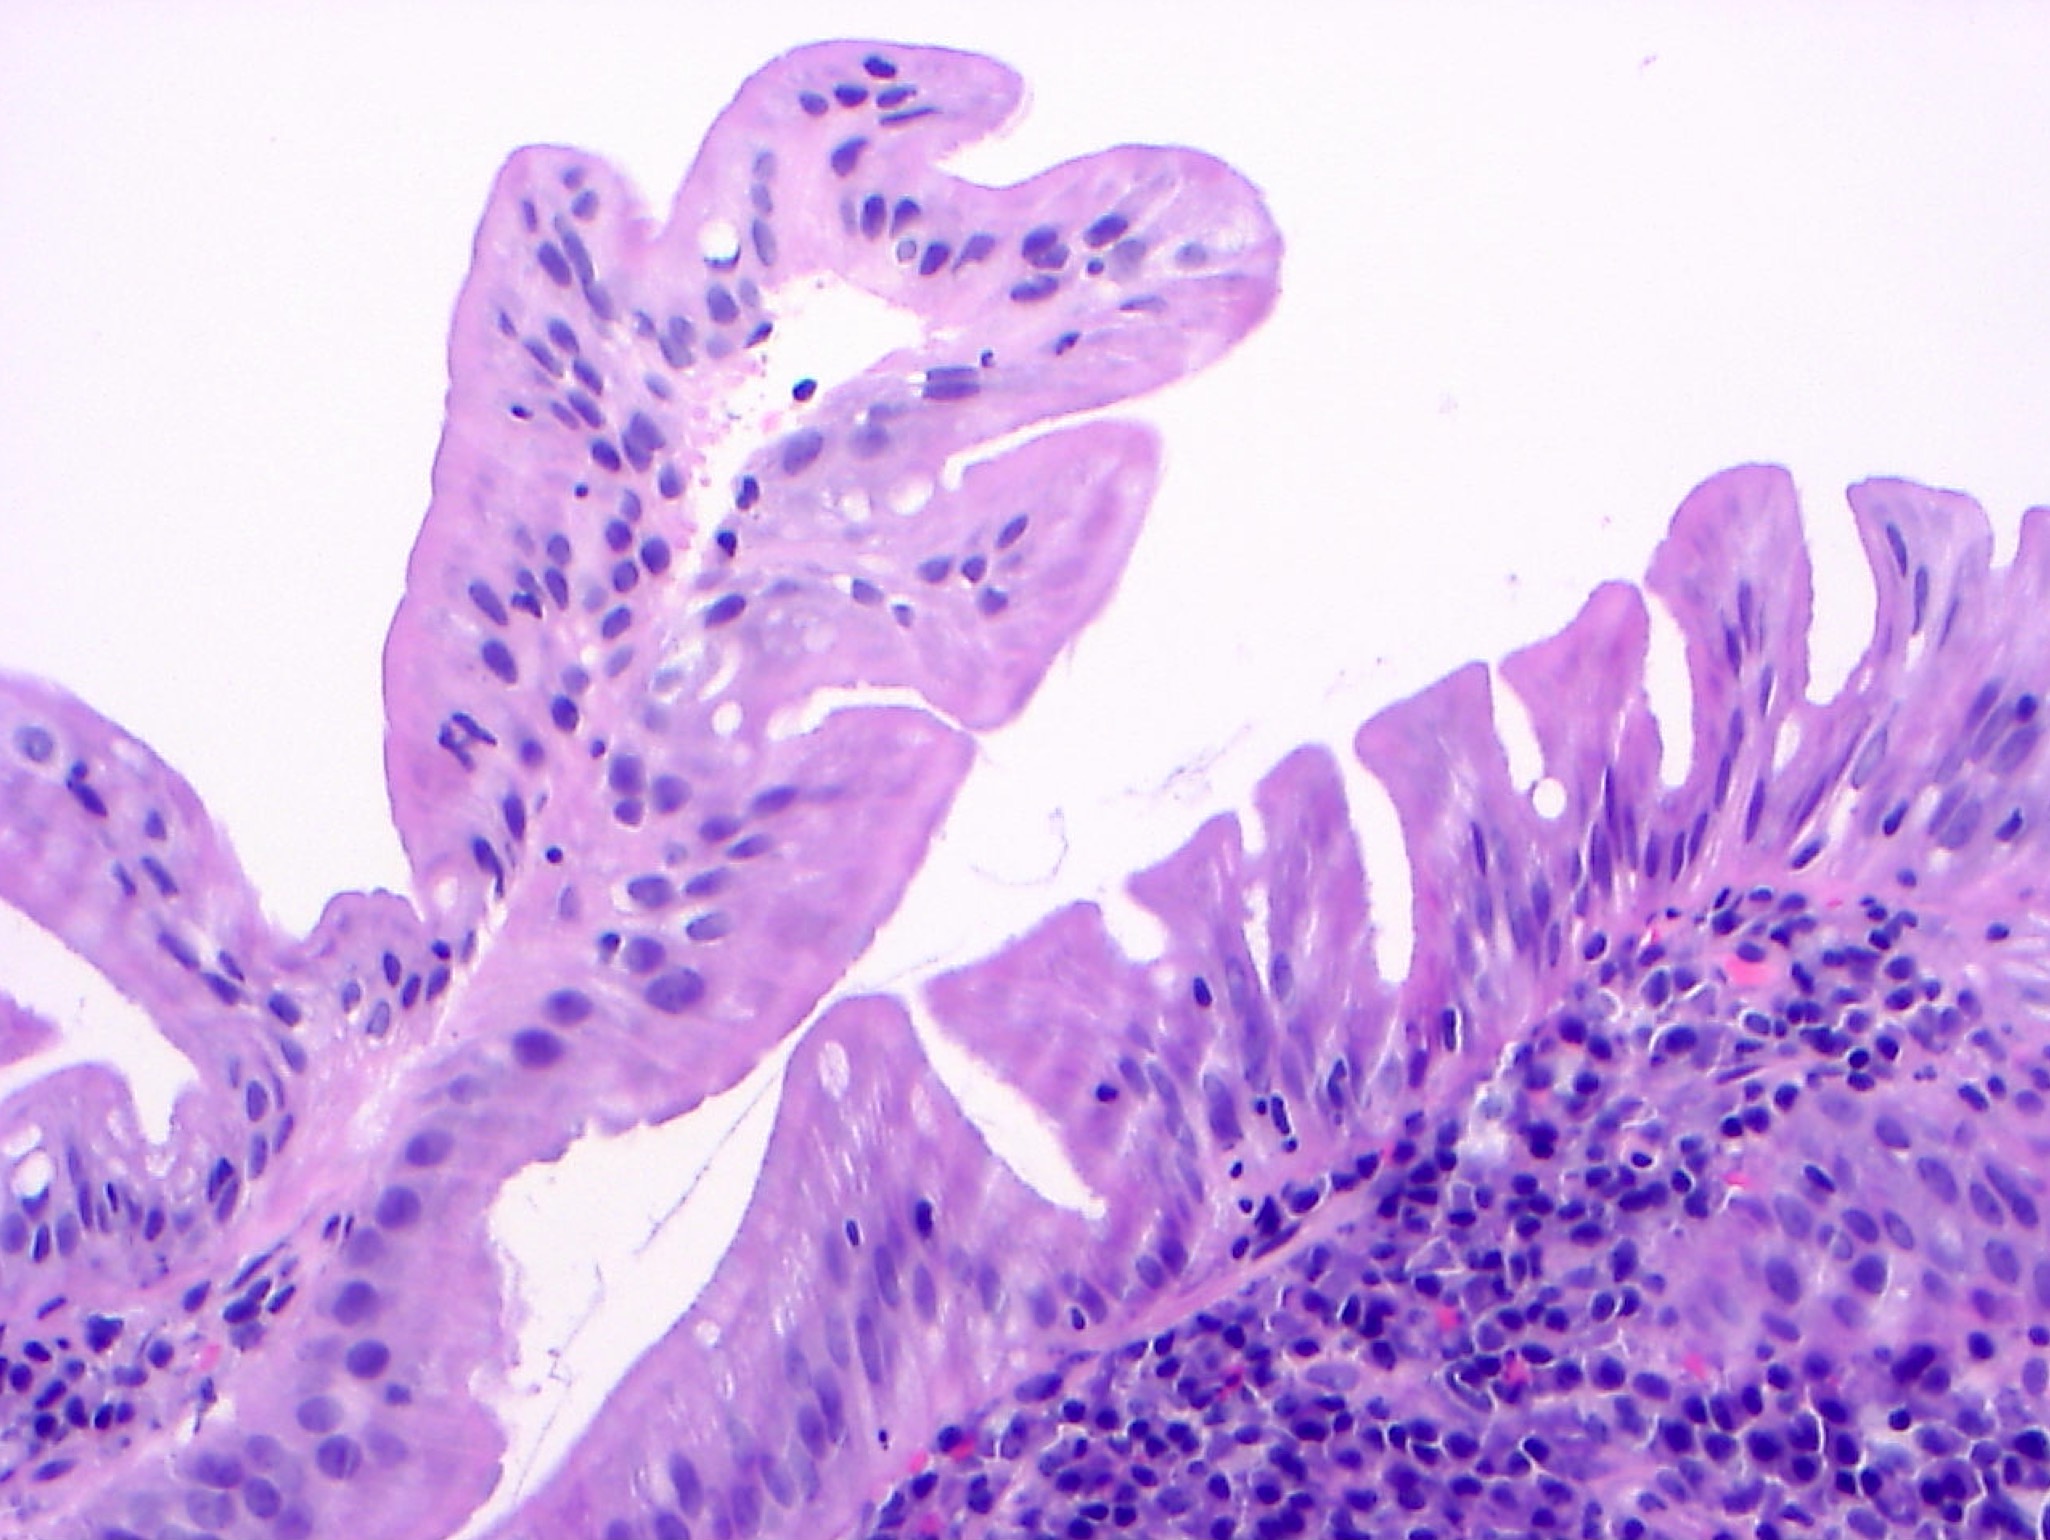

Microscopic (histologic) description

- Low grade dysplasia:

- Preserved nuclear polarity

- Pseudostratified, crowded, elongated and hyperchromatic nuclei

- Lack of surface maturation, i.e. abnormalities persist to surface

- IBD associated nonconventional dysplasia (i.e. not intestinal type) has been described and is relatively common in IBD patients:

- Nonconventional dysplasia subtypes (Histopathology 2021;78:814, Hum Pathol 2020;100:24, Mod Pathol 2020;33:933):

- Hypermucinous (mucinous) dysplasia:

- Tubulovillous or villous architecture with prominent mucinous differentiation

- Usually mild nuclear atypia, especially towards the surface

Microscopic (histologic) images